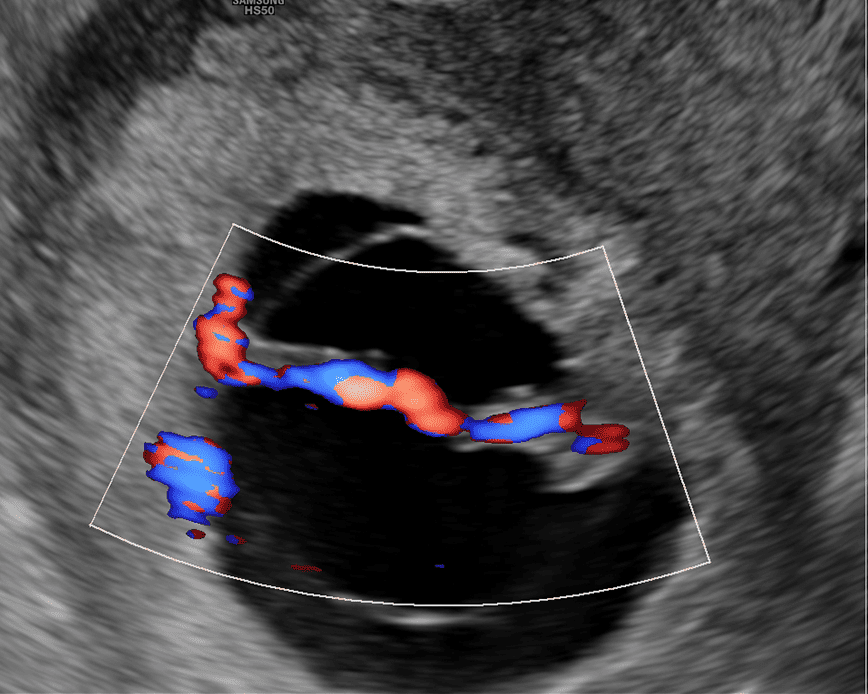

Esta ecografía sirve para evaluar la hemodinamia materno-fetal y detectar problemas de crecimiento como el RCIU (Restricción del Crecimiento Intrauterino) y el riesgo de preeclampsia (presión arterial alta durante el embarazo). Además, nos permite evaluar el cordón umbilical y detectar circulares de cordón simple, doble o triple.